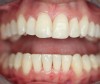

Case 2 demonstrates composite restoration following orthodontics. Surface concavities on the facial of the lateral and central incisors, papillae loss between the central incisors, severe incisal wear on left central incisor, and a poorly shaped right lateral incisor were restored with composite. Placement of a clear matrix that reflected the gingiva allowing subgingival bonding and composite placement closed the gingival embrasure between the central incisors (Figure 4 and Figure 5).

Figure 4  Teeth with multiple surface and structural defects required improving the smile design following orthodontics.

Figure 4

Figure 5   Final composite restorations of the four maxillary incisors.

Figure 5